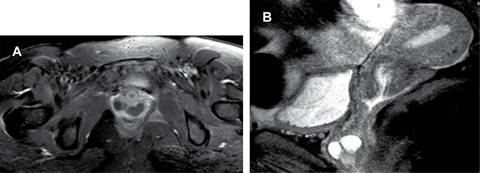

Figura 2: Resonancia magnética de pelvis (A) axial T1 FAT SAT GAD con realce de tejidos blandos de tipo periférico del quiste de Gartner (B) sagital T2 FAT se observa lesión quística multiloculada en el tercio inferior de la pared vaginal anterior.

Femenino de 31 años de edad que refiere abultamiento en región periuretral asociado con datos de disuria de dos semanas de evolución. Acude a médico particular, el cual refiere tumefacción parauretral con extensión a pared vaginal anterior y solicita estudio de resonancia magnética de pelvis contrastada, en la que se observan imágenes saculares bien delimitadas hipointensas en la secuencia T1 e hiperintensas en T2, de aspecto agrupado, que tras la aplicación de medio de contraste no presentan realce significativo, localizadas en el muro anterior del tercio distal de vagina con diámetros aproximados en el plano sagital de 1.9 cm, coronal 3.4 cm y axial 3.5 cm, situadas a 1.1 cm del introito vaginal y a 3 cm del cérvix uterino. La uretra se observa respetada sin datos de disrupción de los esfínteres. Impresión diagnóstica: imágenes quísticas en tercio distal y anterolateral de vagina que sugieren la posibilidad de quiste de Gartner (Figuras 1 y 2).